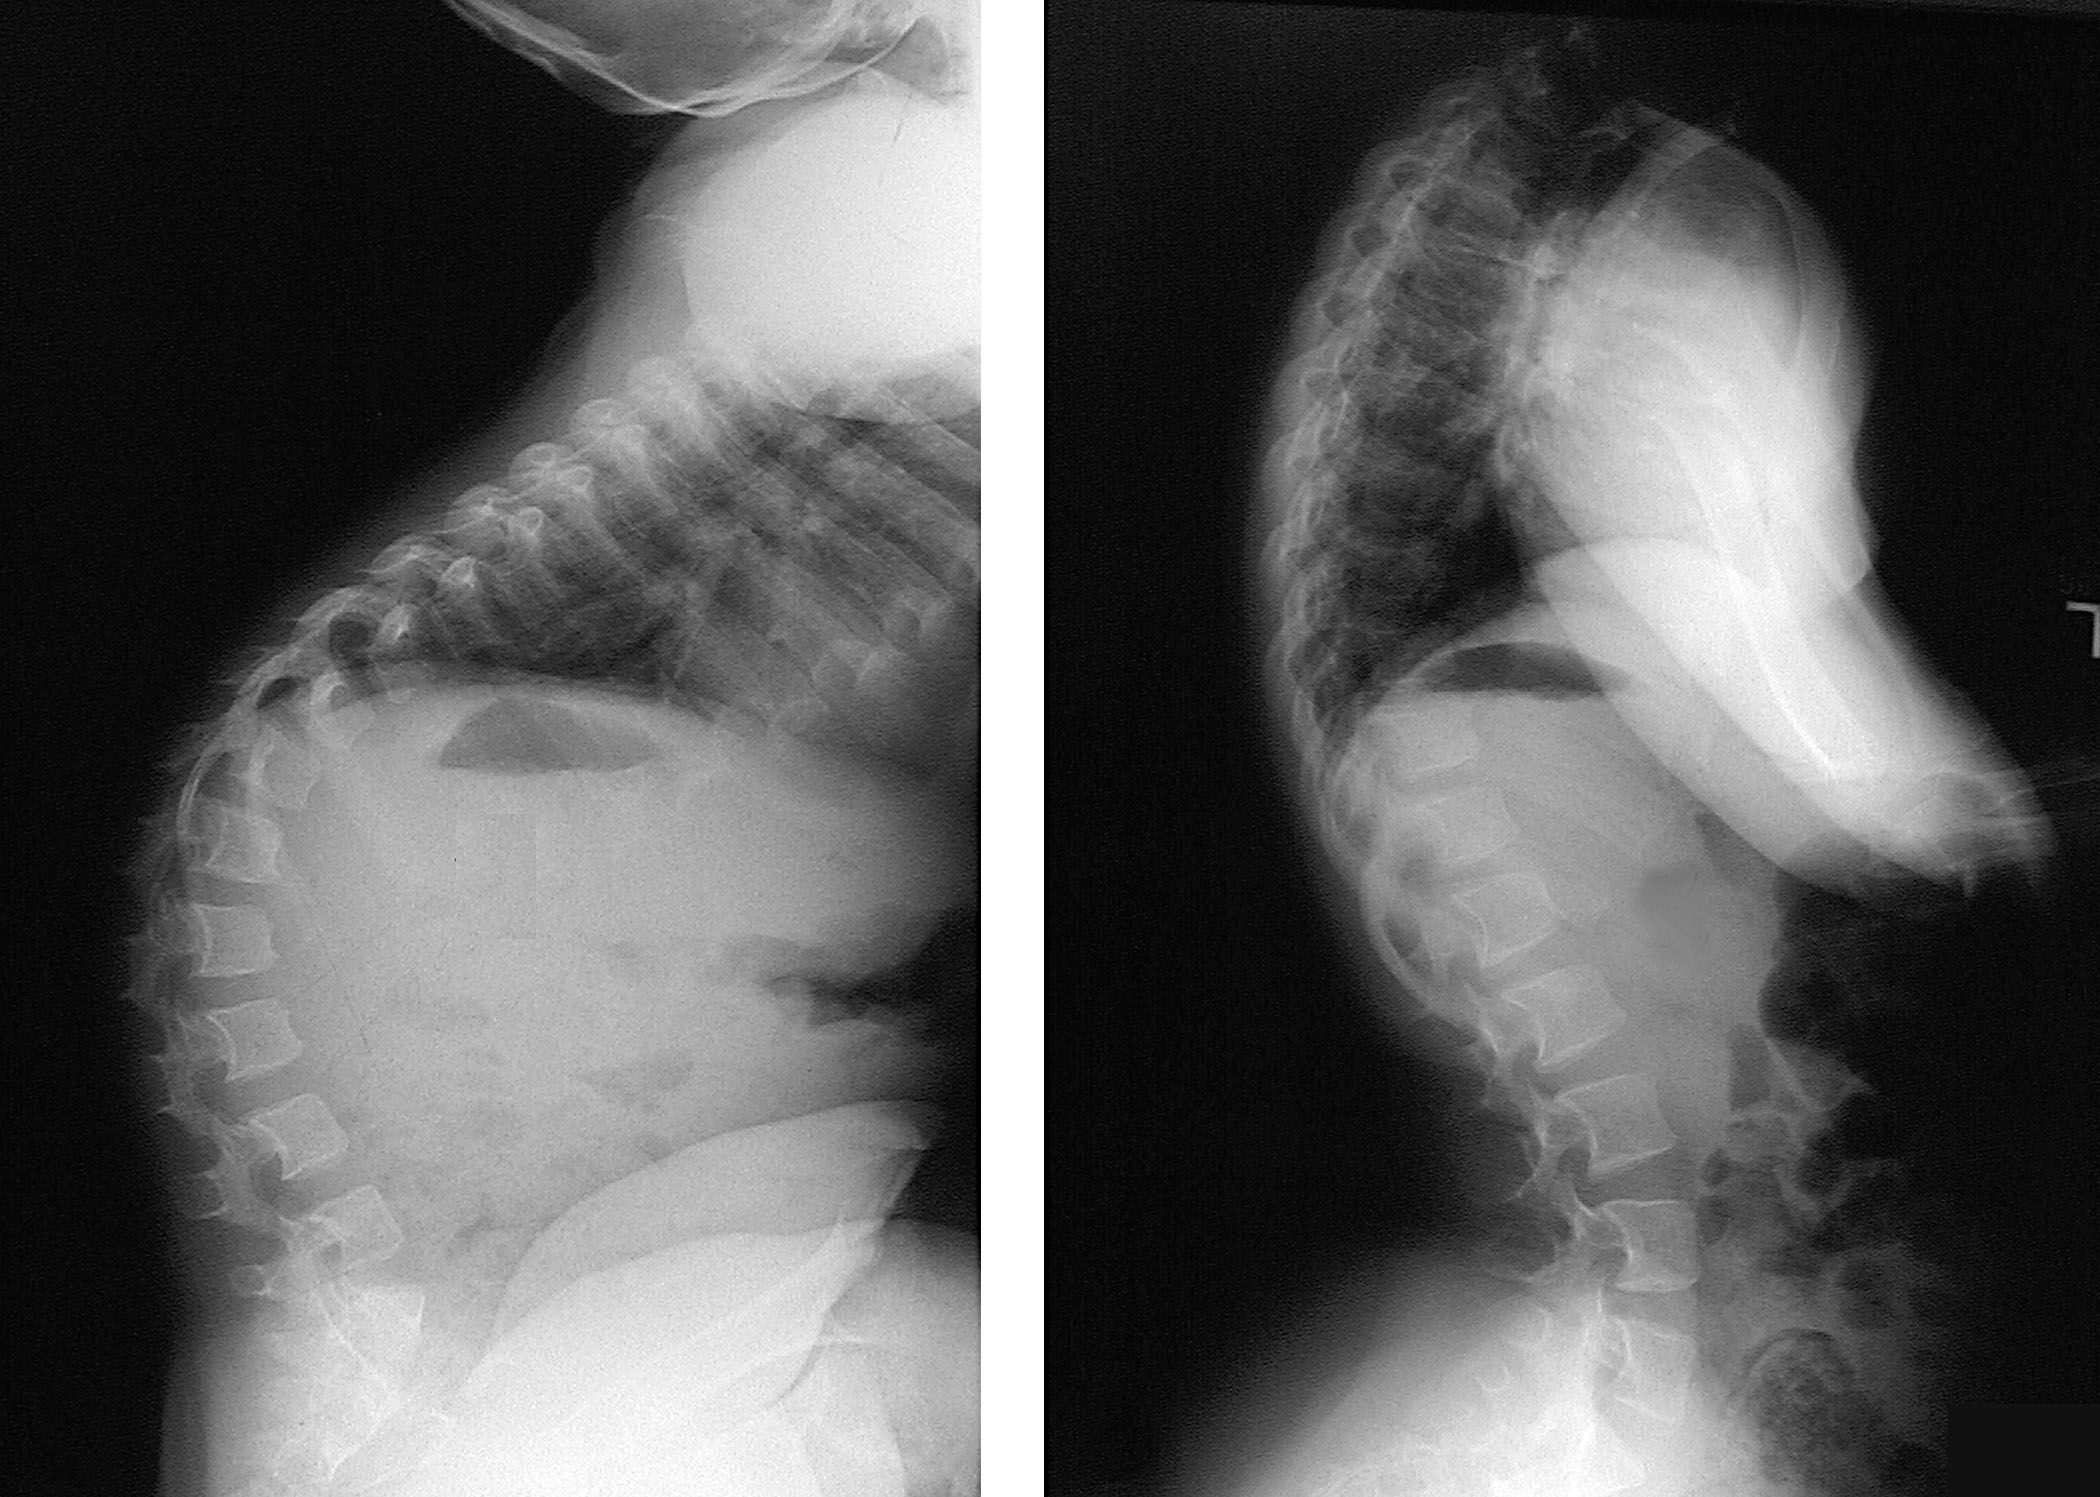

X-ray of kyphosis

(Left) X-ray of a child with achondroplasia shows a kyphotic curve in the upper back. (Right) The curve has corrected itself over time, which is common in children with achondroplasia.

Reproduced from Vaccaro AR (ed): Orthopaedic Knowledge Update 8. Rosemont, IL. American Academy of Orthopedic Surgeons, 2005, pp. 663-675.